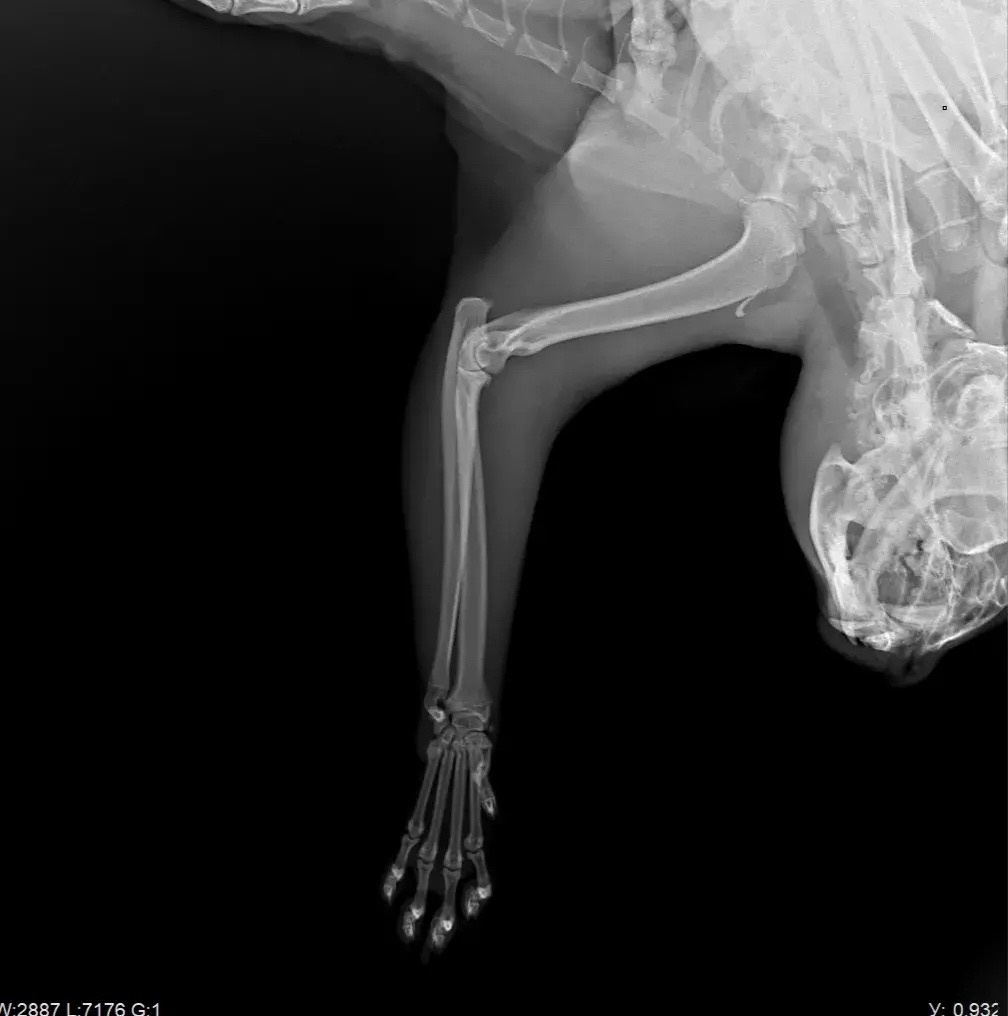

Это ещё не всё. Поступил новый разодранный котик, в запущенном состоянии совсем. Лапа разодрана, болит, кровоточит. Самое главное, что мы сделали РЕНТГЕН и у котика какашки стоят колом, клизма НЕ помогает, нужно оперировать, а это снова деньги. До операции нужно СДАТЬ АНАЛИЗЫ, ни один адекватный врач не возьмётся оперировать животное, о состоянии которой ничего не известно. Любая операция - ЭТО НАРКОЗ! Огромные риски…. а ведь мы же все таки хотим СПАСТИ, а не угробить…